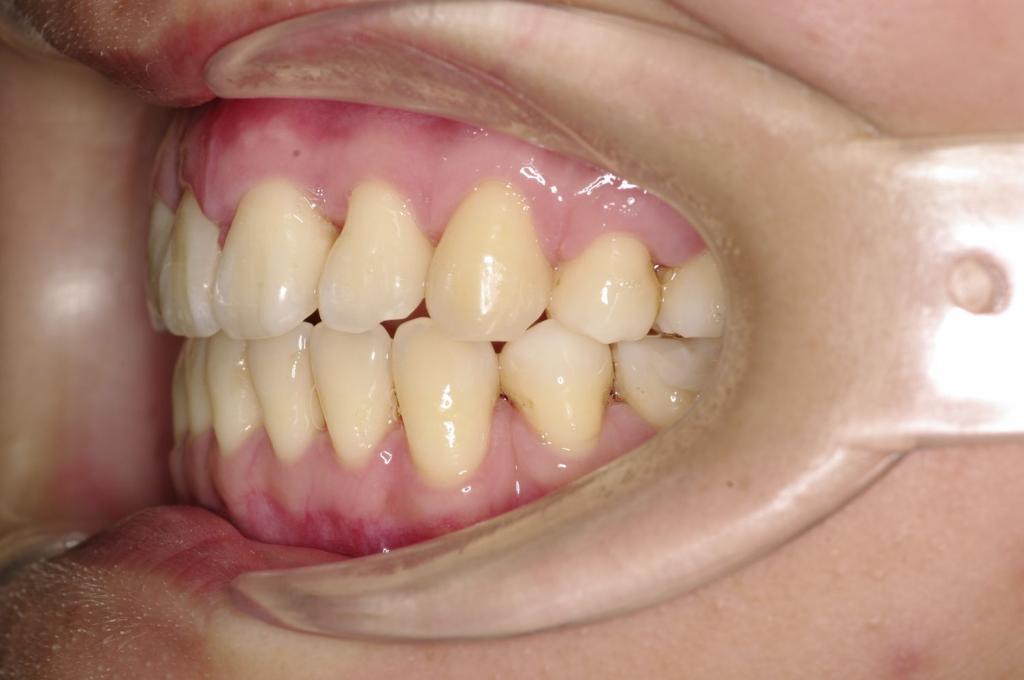

前歯、出っ歯・開咬の矯正治療

(治療期間、治療前後写真、治療方法、費用)WORKS